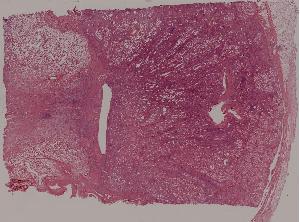

36. Lymphoma